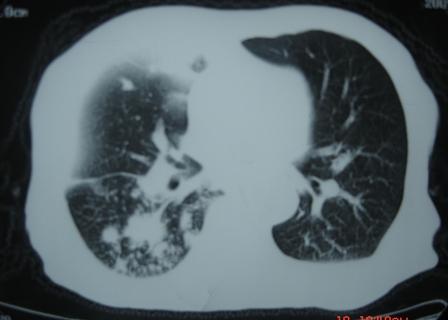

xx 男 63岁 发热 家属描述有时高热 有时低热 抗酸杆菌阴性 于2月21号 胸片及ct

结核空洞并播散

右肺上叶干酪性肺炎并两肺支气管播散。

考虑右肺上叶干酪性肺炎并支气管播散。

楼主  :谢谢大家发言  我和大家考虑的一样干酪性肺炎并播散